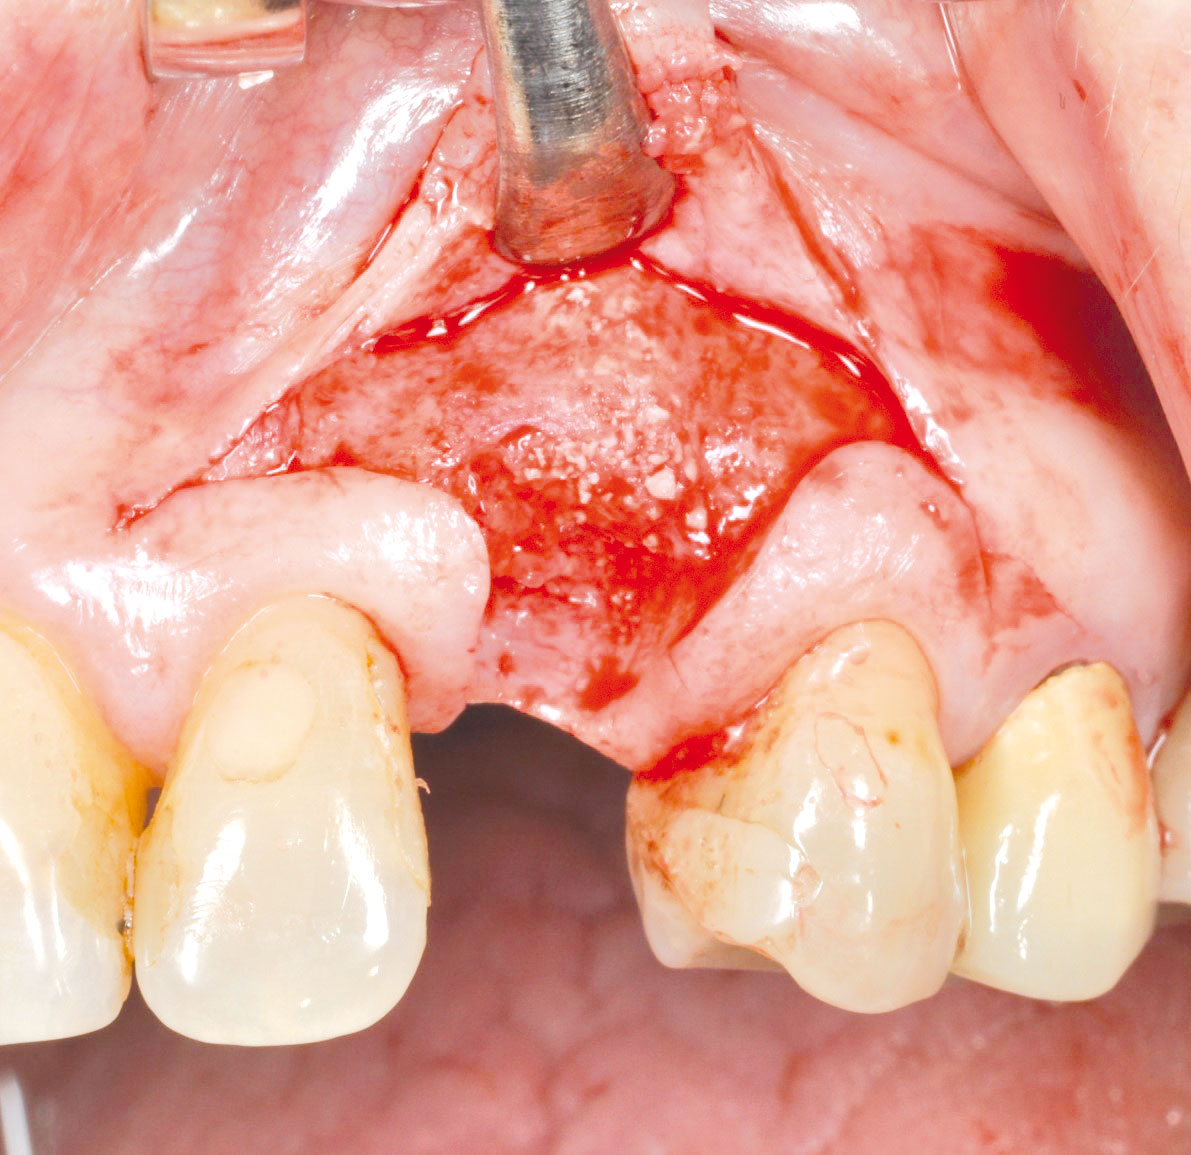

GBR with cerabone® and Jason® membrane in the front tooth region - Dr. H. Maghaireh

Initial clinical situation with gum recession and labial bone loss eight weeks following tooth extraction